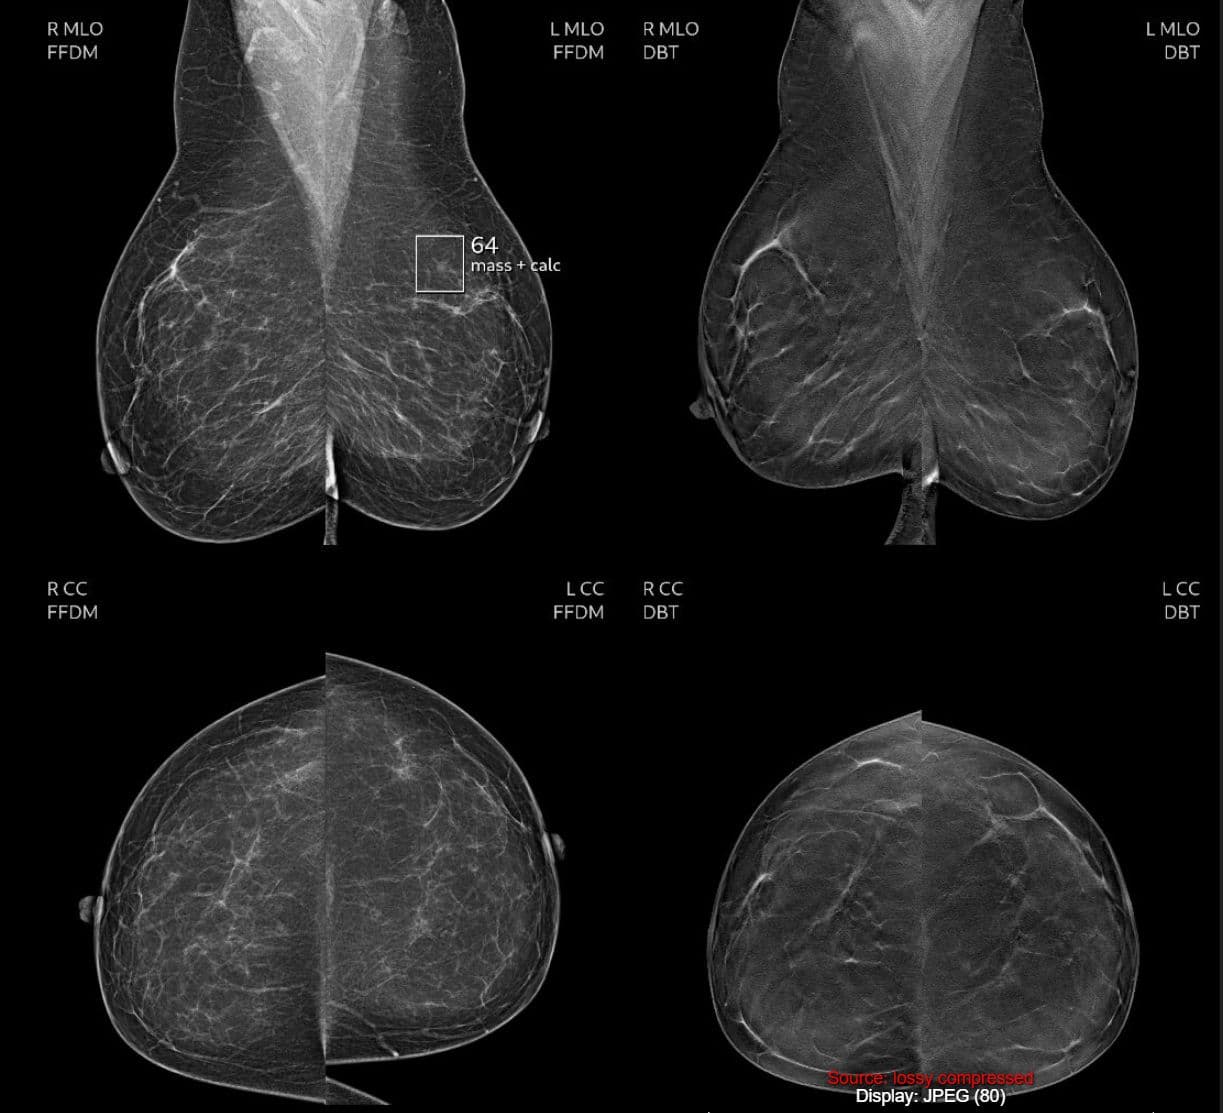

Mammography Screening

Routine mammograms remain one of the most effective tools for detecting breast cancer early when treatment outcomes are often most successful.

Hoskinson offers self pay mammograms for $155, helping make this important screening more accessible for patients seeking clarity and peace of mind.

• Breast MRI for advanced breast imaging when additional evaluation is needed